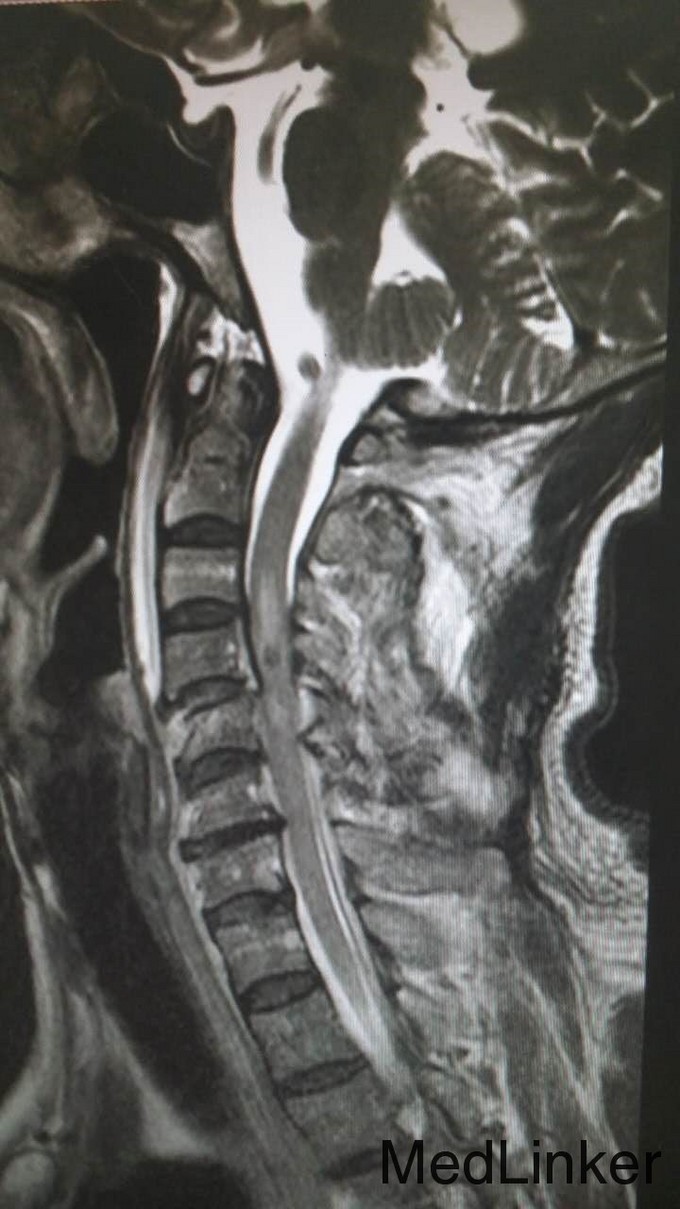

主诉:头颈部重物咂伤5小时伴四肢瘫 病史:入院5小时前,头颈部被门板砸伤,伤后全身疼痛,伴四肢瘫。

查体:T4平面以下痛觉消失,四肢肌力0级。双侧病理征阳性。 辅检:全身CT示:C4左侧椎扳、侧块、C5-6左侧横突多发骨折,C5椎体压缩骨折,C4椎体滑脱,颅内未见明显血肿,胸腹盆末见明显外伤行病变。头颅MRI示:C3-6水平颈髓出血伴水肿。

诊断:1.C3-6水平颈髓损伤出血伴水肿,2.C4左侧椎扳、侧块、C5-6左侧横突多发骨折,3.C5椎体压缩骨折,4.C4椎体滑脱(Ⅰ度) 治疗:伤后5天,予行C3-6椎板切除、椎管减压,侧块固定融合术